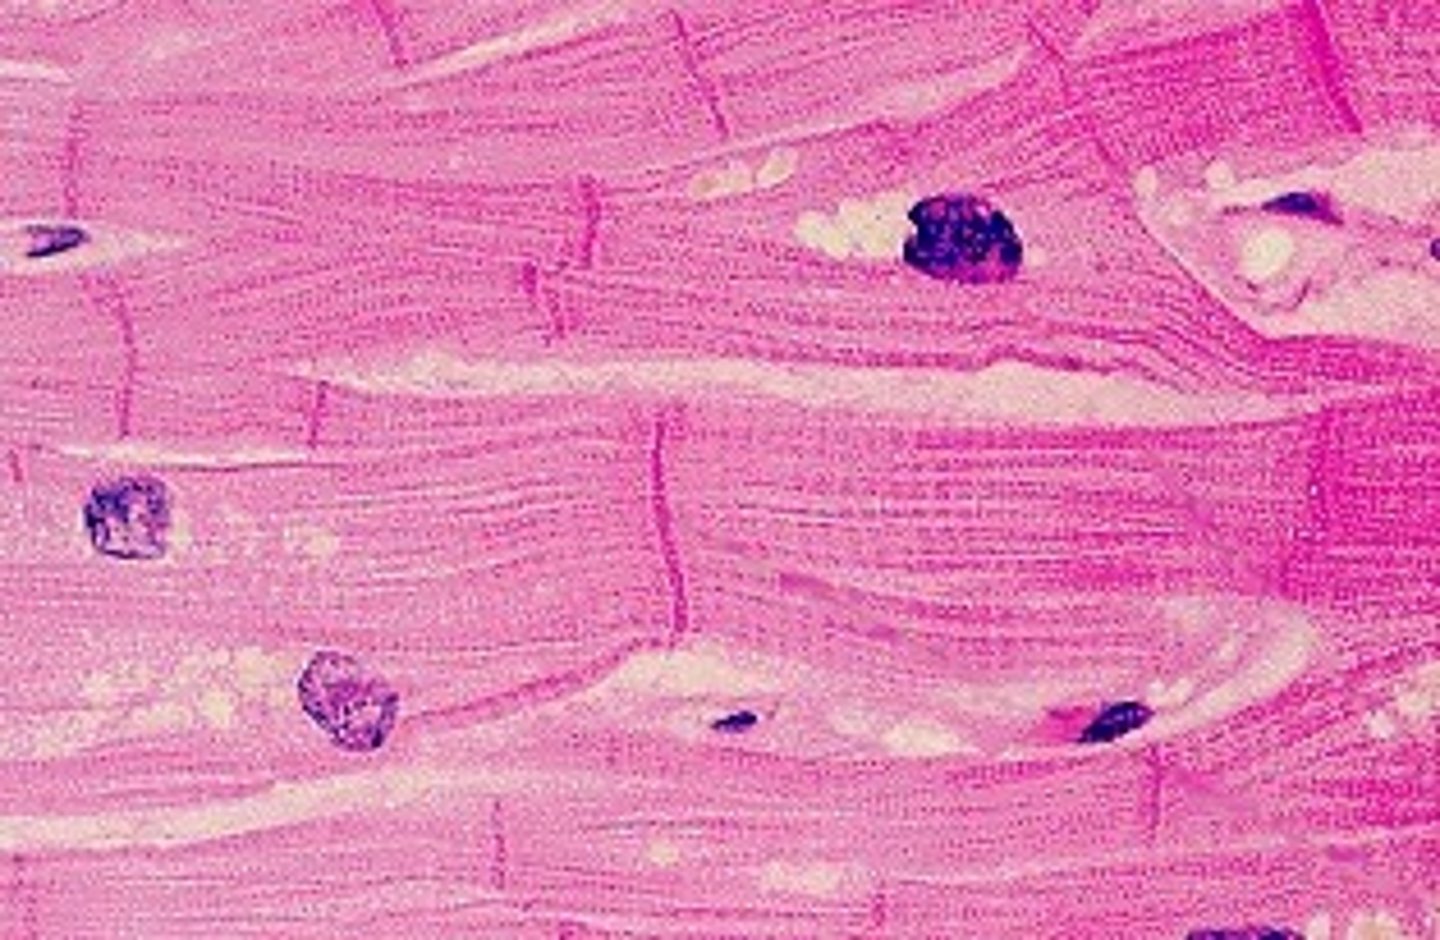

cardiac muscle is

a. striated

a. striated

cardiac muscle

involuntary

cardiac muscle is _____-nucleated

mono-nucleated (1 nucleus)

intercalated discs

junctions between cells anchor cardiac cells